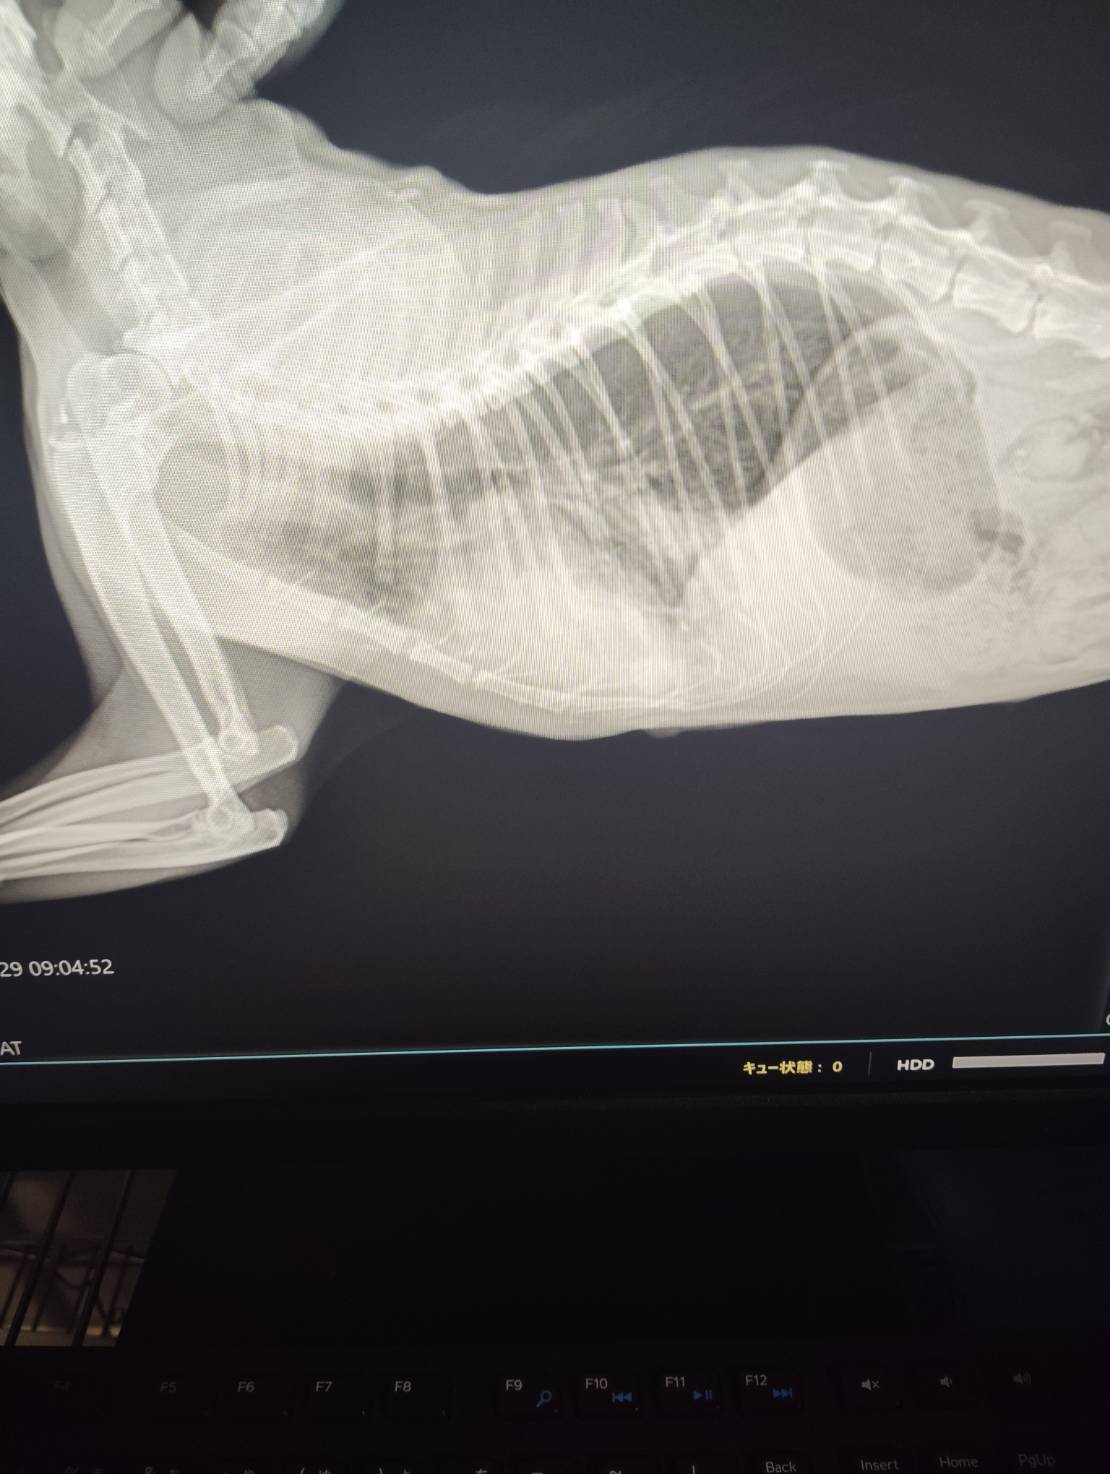

- 腹部触診で結腸部に硬い糞便を触知

- レントゲン検査にて結腸拡張(便塊の貯留)を確認

→ 診断:慢性便秘